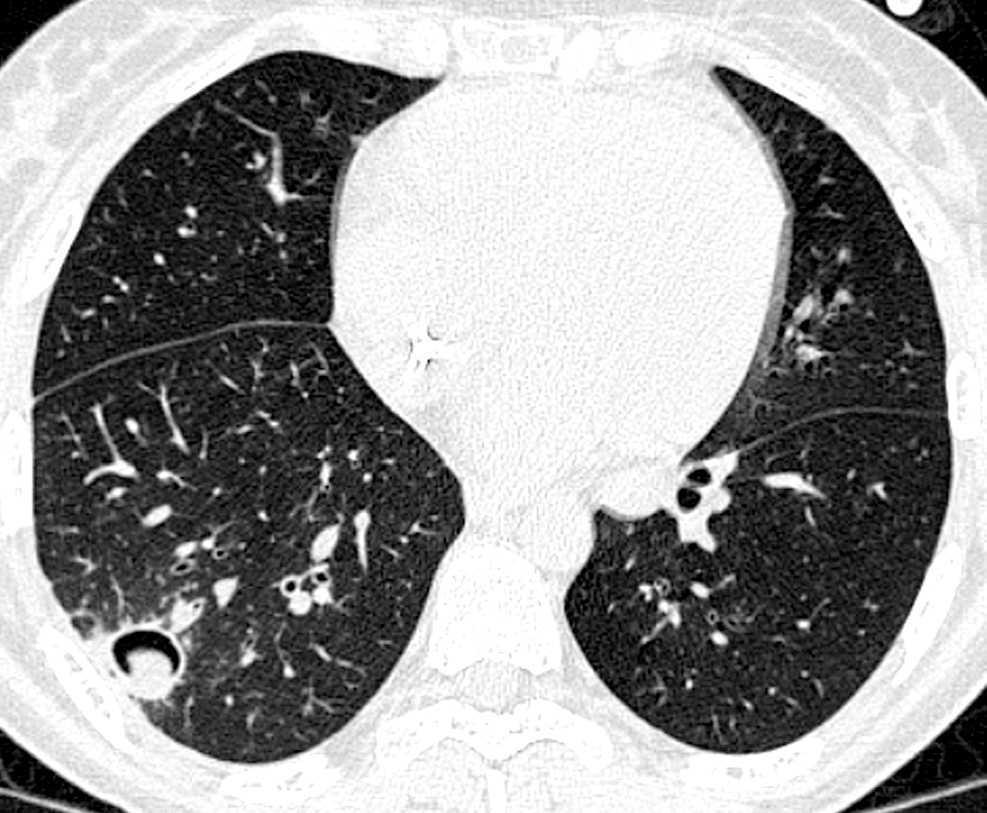

En este período el microorganismo más importante es el CMV. Por ello debe hacerse énfasis en las medidas profilácticas anteriormente descritas. El tratamiento preventivo ha sido uno de los grandes avances en este campo y consiste en el tratamiento de la infección, detectada por antigenemia o PCR en sangre o en LBA, con ganciclovir o foscarnet antes de que aparezca enfermedad. Si se desarrolla una neumonía intersticial por CMV (fig. 4) el tratamiento con ganciclovir asociado a inmunoglobulinas permitirá su control en el 30-50% de los casos. También en este período aparecen infecciones fúngicas. Aunque no es objetivo de esta monografía el extenderse en el tratamiento de estas infecciones, únicamente señalar que el tratamiento inicial de la aspergilosis invasora es voriconazol y el de la candidiasis puede ser caspofungina o anfotericina B (o sus formulaciones) y una vez conocida la especie, si es sensible a fluconazol se puede continuar con dicho agente.

Figura 4. Neumonía intersticial por CMV.